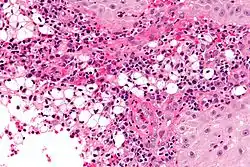

| Photogravure of rhinoscleroma from Wolkowitsch. | |

A positive culture in MacConkey agar is diagnostic, but cultures are only positive in 50–60% of cases. Diagnostic characteristics are most commonly found in the granulomatous stage and are described as being plasma cells with birefringent inclusions, Russell bodies, pseudoepitheliomatous hyperplasia, and groups of large vacuolated histiocytes containing Klebsiella rhinoscleromatis (Mikulicz cells).[2]